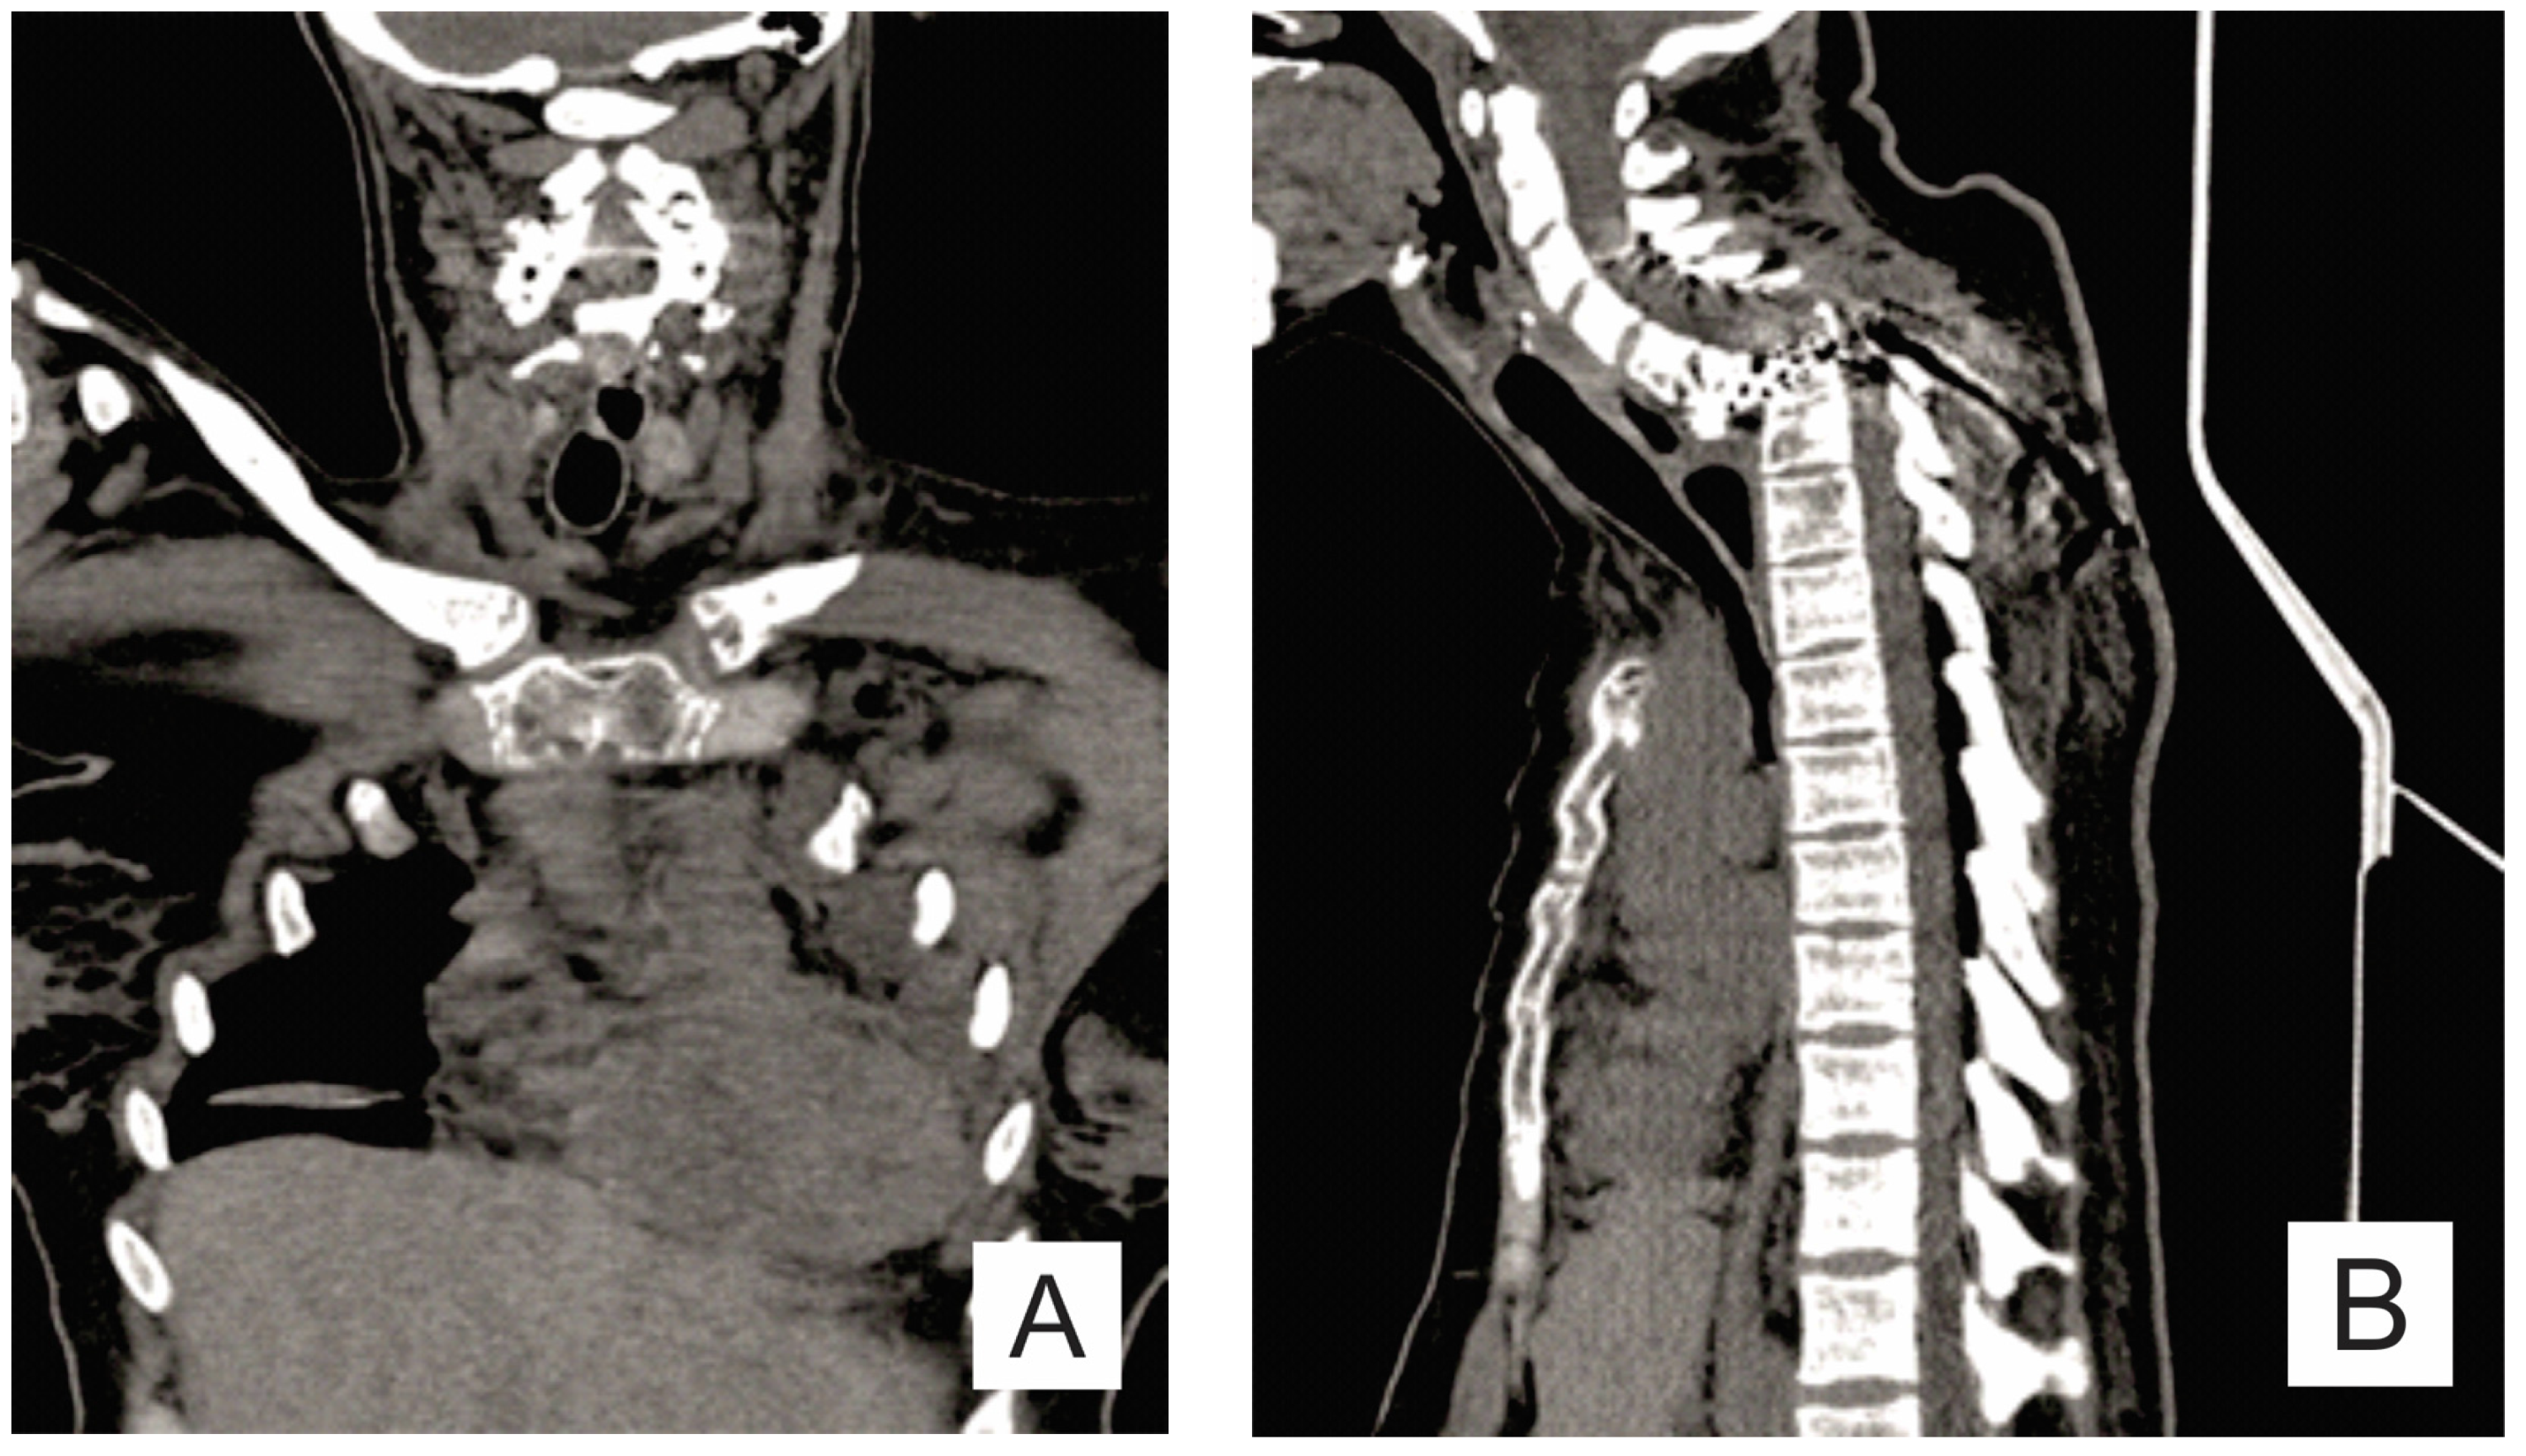

2. Case Report